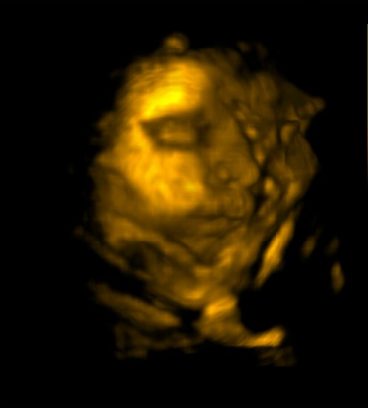

Behold, our baby’s face : )

He had his hands up by his face most of the time, but we got several clear shots. It was a fun experience! I will actually have a video to share too – pending! And a few more photos – including a nice smirk : )

Our appointment was next – 3D times with the baby! Even more than his profile, it was awesome to get to see his orientation in there. Now I realize why I get all my kicks on the right side – and his butt under my ribs all the time!